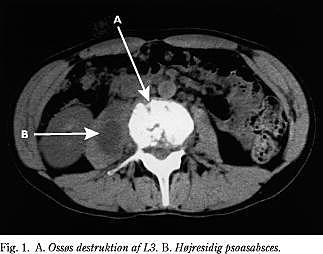

Røntgenbilleder af columna lumbalis viste destruktion af dækpladerne omkring 3. discus og udslettet højresidig psoasskygge. Blodprøverne viste: SR 60, CRP 65 mg/l, negativ hiv-antistof, negativ bloddyrkning, normal leukocyt- og differentialtælling, normale immunglobuliner og levertal. Røntgen af thorax viste normale forhold. CT af columna lumbalis viste destruktion af nedre dækplade af L3 og øvre dækplade af L4 med en stor højresidig psoassænkningsabsces (Fig. 1 ), der strakte sig til lig. inguinale dx.